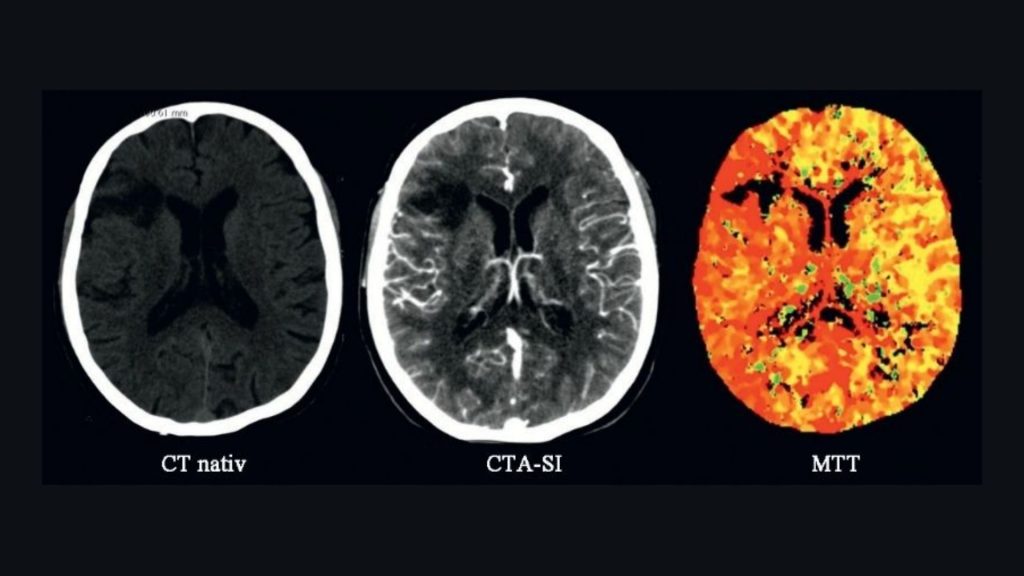

Investigaţii neuroimagistice speciale. Aplicații în patologia neurologică

Autor: Dr. Mircea Medrea Investigaţii neuroimagistice speciale. Aplicații în patologia neurologică I. PWI (PERFUSION WEIGHTED…